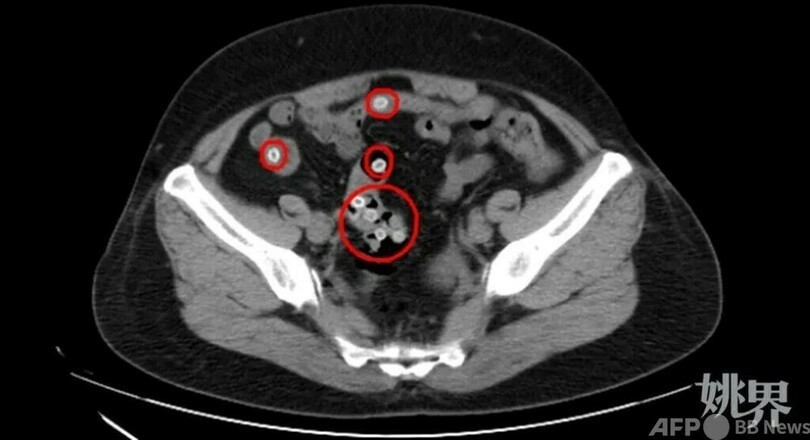

CT検査をすると、王さんの腸内には類円形の高密度の影がいくつもあり、びっしりとした円形の白い点は腸内に滞留しているヤマモモの種で、腹痛を引き起こした原因だと分かりました。